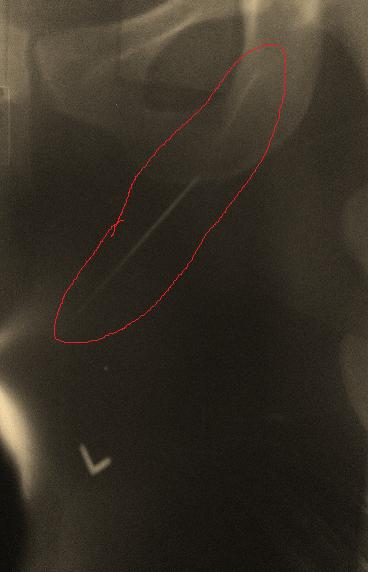

Sewing needle in her leg!!

Do you see the red circle? Well, that is a sewing needle that got logged into her adductor muscles right behind her pubic bone on the left side….SERIOUSLY?!?!

She told me that when she sat down in that car (when the pain first started) she felt an immediate bout of pain but had no idea why. She was moving apartments and apparently a needle was sticking up from the car seat and BAM…right in the leg. How there was no blood or sign of the needle for almost 3 weeks (from time of injury to time of xray) is astounding to me.  I also have no idea how my treatment abolished her pain for almost a full week…yes, she literally resumed her life pain free until squatting at the gym made her sore again.

Anatomically, let’s think of how lucky she was…aside from all the muscles she must had hit with that needle, she also has one more major anatomical structure she avoided…can you guess what it is?

The needle could have easily hit her femoral artery causing a whole host of other issues! Yikes!